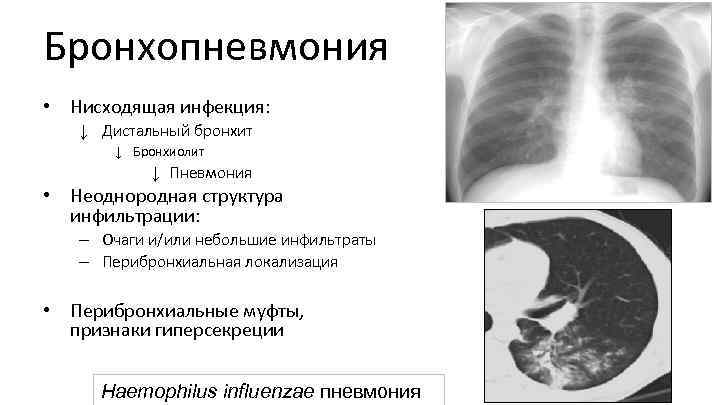

Бронхопневмония • Нисходящая инфекция: ↓ Дистальный бронхит ↓ Бронхиолит ↓ Пневмония • Неоднородная структура инфильтрации: – Очаги и/или небольшие инфильтраты – Перибронхиальная локализация • Перибронхиальные муфты, признаки гиперсекреции Haemophilus influenzae пневмония